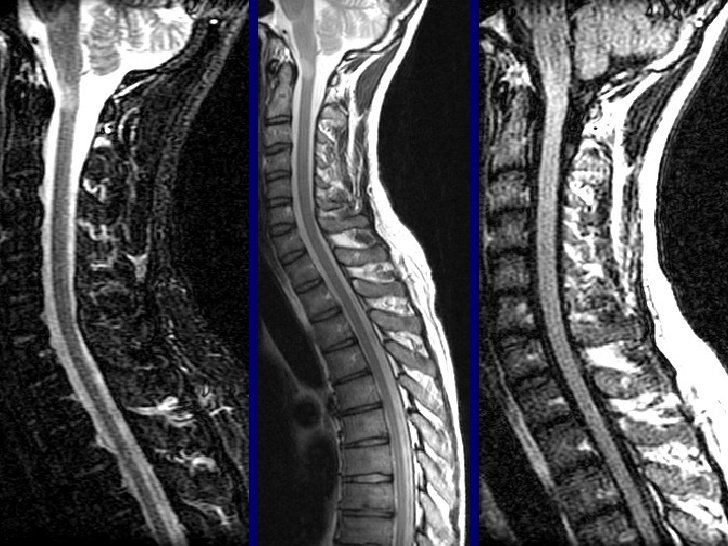

Thoát vị đĩa đệm xảy ra khi nhân nhầy bên trong đĩa đệm cột sống bị đẩy ra khỏi vị trí bình thường, gây áp lực lên ống sống và các dây thần kinh xung quanh. Điều này dẫn đến các cơn đau nhức khó chịu ở vùng cổ, vai, gáy hoặc thắt lưng.

Nguyên tắc cơ bản trong chữa thoát vị đĩa đệm là lựa chọn phương pháp điều trị tương thích với giai đoạn bệnh. Các phương pháp có thể bao gồm điều trị nội khoa (dùng thuốc), vật lý trị liệu, can thiệp thần kinh và phẫu thuật.